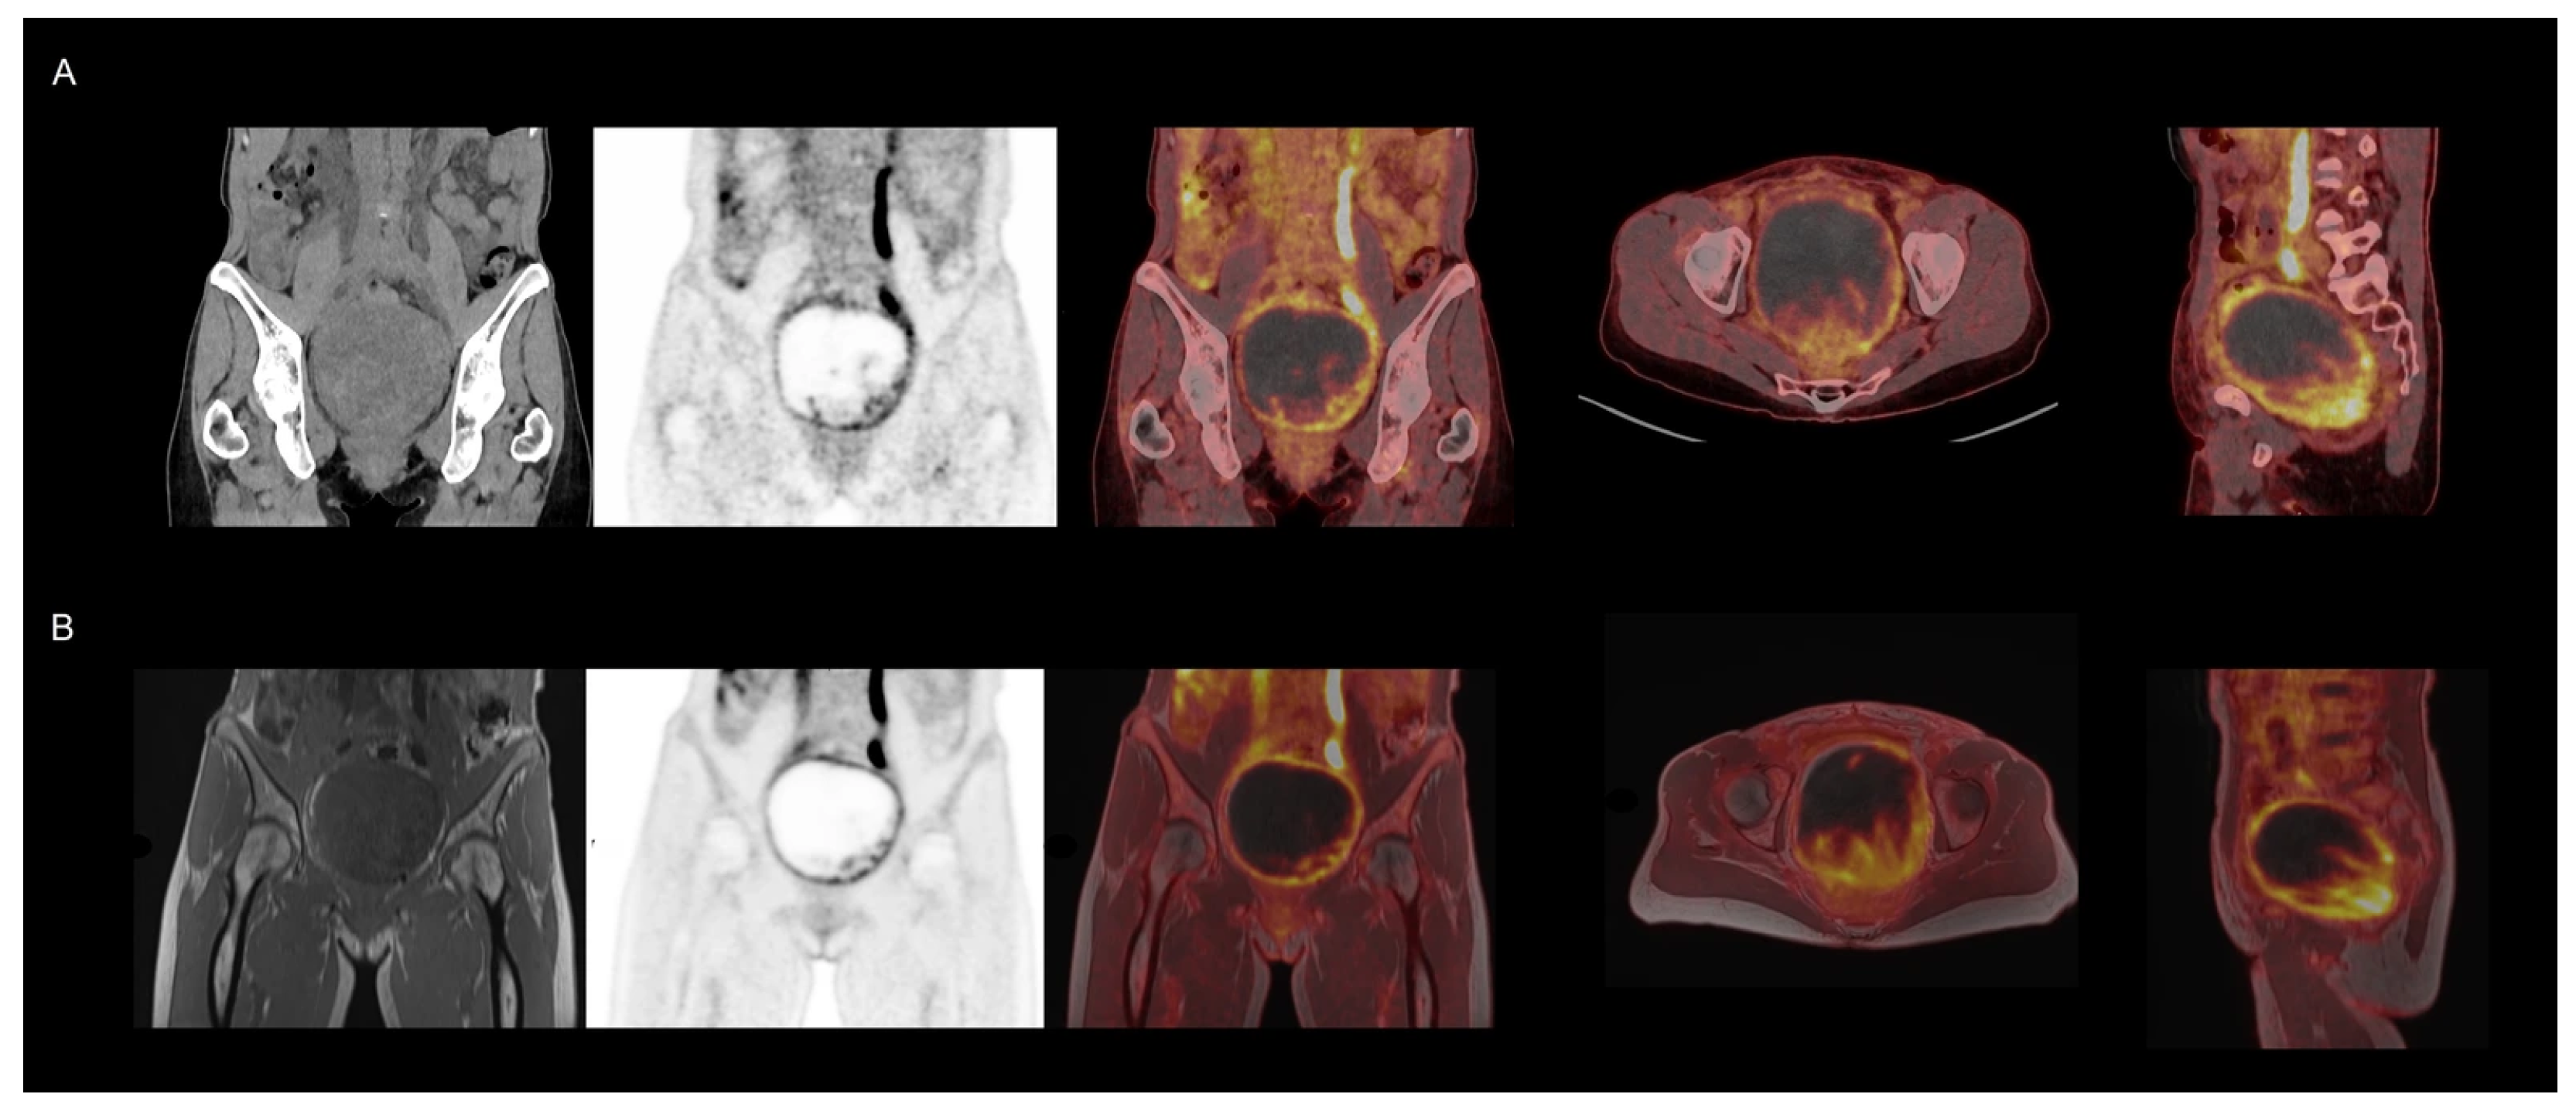

| Female pelvis ([18F]FDG) | 29:17 | 28:38 | 1.6 [1.5;1.9] | 2.9 [2.5;2.9] | 2.5 [2;3] |